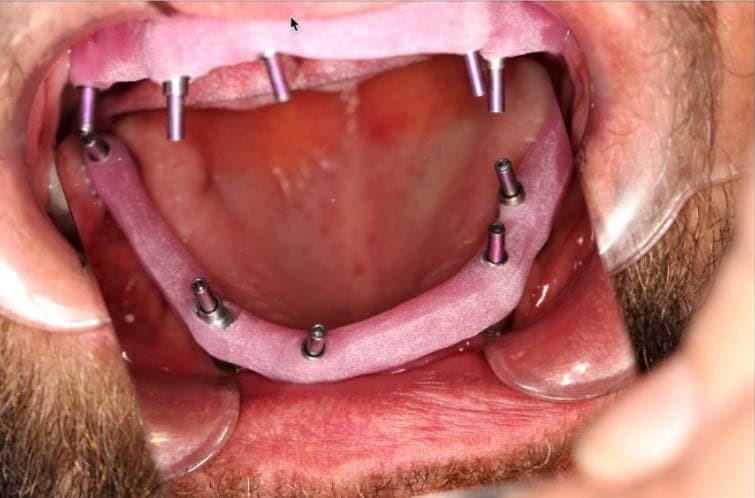

Снятие слепков:

Определение прикуса: